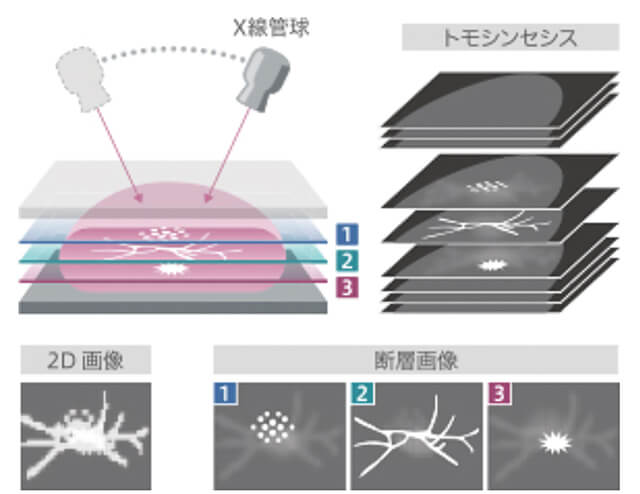

マンモグラフィー部⾨

当センターではマンモグラフィ検査の診断⽤装置として新しくFUJIFILMの「AMULET Innovality」を導⼊しました。この装置ではこれまでより低線量で⾼画質な画像の提供が可能となり、検査に来られる患者さんの負担をできるかぎり軽減することを考え、充実した検査の向上に努めてまいります。

ここではこの装置の説明として、以下の特徴を紹介します。

新たな機能「トモシンセシス」

マンモグラフィ検査では、通常誰にでも⾒られる乳腺は診断⽤画像で⽩く写ってしまい、特に⾼濃度乳腺のような⽅の場合であると、この乳腺の中に疾患が隠れてしまうことがあります。検査時には乳腺に隠れるくらいに⼩さく早期の腫瘍であっても、約100⽇〜半年ほどで倍の⼤きさになると⾔われており、早期発⾒へと繋げるためにはいかにこの⼩さな腫瘍を発⾒できるかにかかっています。そこでこの度新たに加わる機能としてトモシンセシスを⾏えるようになりました。X線管球が胸の上を連続的に移動し、複数の画像を重ね合わせることで、⽴体的な画像を構成し、乳腺との重なり部分等をより詳しく観察できるようになったため、従来の⼆次元の画像では発⾒の難しかった疾患も容易に観察できるようになりました。

⾼画質な画像の提供

画像の観察を⾏ううえで、乳房の中にある⼩さな⽯灰化や腫瘍等をきれいに細かく写すことは⾮常に重要となります。そこで、今回の装置では画像認識技術によって患者さんごとに体内の⽴体構造を捉え、ざらつきの無い画像を提供できるようになりました。

画像認識技術による画像の提供

画像認識技術による画像の提供